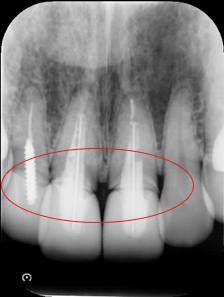

綺麗に被せてあると思っていたクラウン、実は歯肉の中は全然合っていない不完全な治療が多いのです。

綺麗に被せているようにみえますが

エックス線検査をすると歯肉の中で被せ物があってません。

エックス線検査ではしっかりあってます。